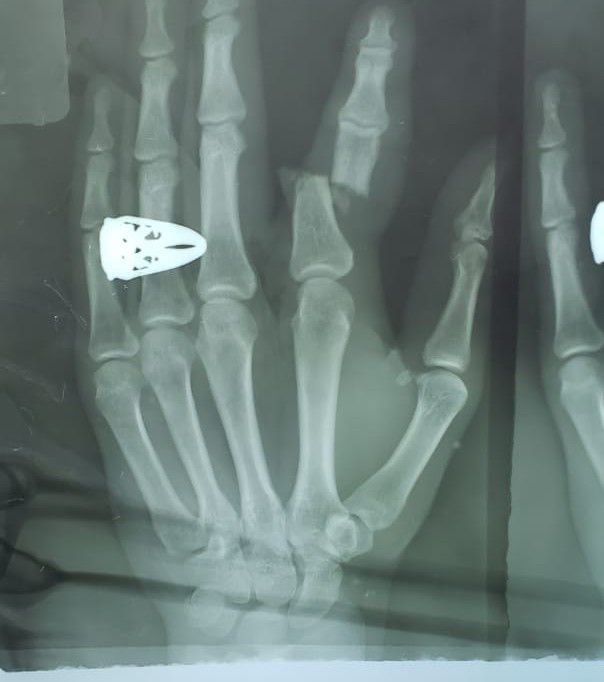

Index finger (left) middle phylnx displaced Fx

Rx = manipulation , needling, dressing e tongue depressor above and below the index finger ,antibiotics ,analgesics , F/U after 14 days e fresh and old xrays